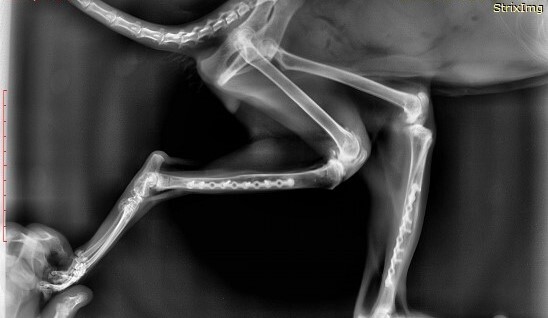

Большая часть зайчат умирает "внезапной смертью" вызванной отказом работы внутренних органов, сопровождаемым сильными болевыми ощущениями. Это происходит от обострения хронических проблем, которые копились из-за ошибок в выращивании (некрозы жкт, кровоизлияния в сердечно-сосудистой системе, переломы, защемления нервов, болезни ЦНС и другое). Дикие животные инстинктивно скрывают любое недомогание.